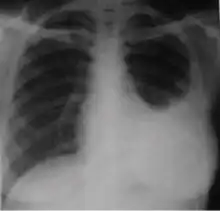

3. Discrete fibrotic scar with volume loss or retraction—Discrete linear densities with reduction in the space occupied by the upper lobe. Associated signs include upward deviation of the fissure or hilum on the corresponding side with asymmetry of the volumes of the two thoracic cavities.

-

Chest x-ray showing distinct fibrotic scar with volume loss or retraction with an upward deviation of the fissure or hilum on the corresponding side with asymmetry of the volumes of the two thoracic cavities.